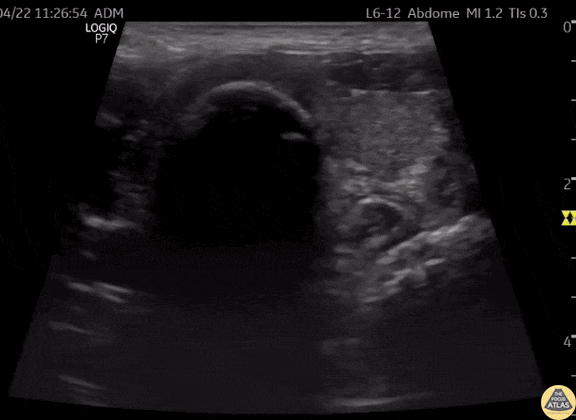

This is a clip of a cervical airway view during intubation attempt. Some artifact is visible in the trachea when passing the tube demonstrating a "Snowstorm Sign" which can be used to confirm the position of an endotracheal tube. In this view it is possible to see the esophagus next to the trachea. As demonstrated there is no motion detected in esophagus during intubation therefore confirming tracheal intubation. Contributor: Renato Tambelli (@R_Tambelli @Jedipocus)